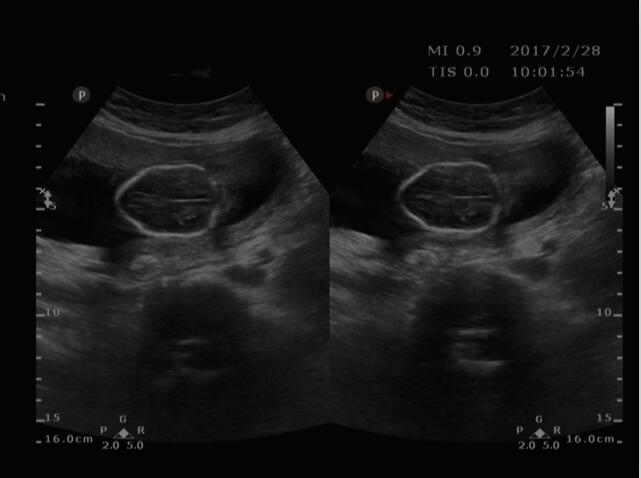

近日,家住商河怀孕4个月的某女士,来我院超声科就诊。接诊大夫为其认真仔细检查,发现该患儿双顶径小于孕周,形态不规则,呈“柠檬头征”,后发现顶枕部一囊性包块,其内含部分脑组织结构,膨出于颅骨外,胎儿其它肢体结构未发现异常。经沟通,此前该女士未做过其它任何检查。随后,该女士在我院办理住院,引产后已证实超声诊断。再进一步了解中得知已孕育两个孩子,其一患有脑积水。

2、缺损处突出一包块,脑膜膨出突出内容物为脑膜,膨出物为囊性肿物,脑膜脑膨出突出内容物为脑膜几脑组织,膨出物为实性回声。

3、大量脑组织膨出时颅骨光环缩小或不规则,双顶径可能偏小。

诊断时难点:缺损较小时缺损及包块不易显示,易漏诊。膨出在一段时间内可能消失,过一段时间又出现。膨出较小时很难区分脑膜膨出及脑膜脑膨出。胎儿的耳朵的超声表现容易和脑膨出混淆。